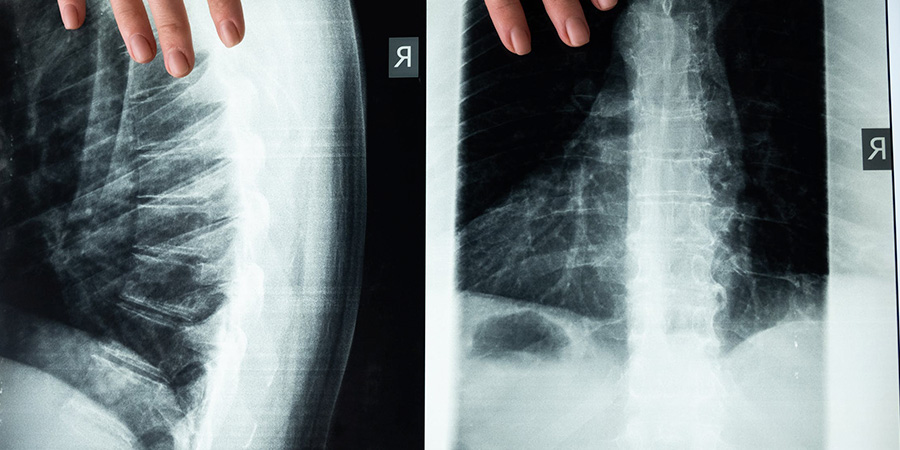

Técnicas mínimamente invasivas de cirugía de columna vertebral

Son muchas las patologías que pueden ser tratadas a través de técnicas no invasivas. Por medio de la aplicación de la endoscopia de columna avanzada es posible tratar lesiones como la hernia de disco lumbar y la estenosis de canal.

La microdiscectomía, en cambio, se indica en pacientes con las lesiones de hernia discal con concordancia clínico o RM, rotura de vértebra o disco invertebral, ciática persistente, espacio único o que los tratamientos terapéuticos conservadores no hayan funcionado.

Estas dos técnicas son aplicadas actualmente en las mejores clínicas de traumatología expertas en columna. Para tener una mejor comprensión de estas cirugías no invasivas, continuaremos con una descripción general de ambas.